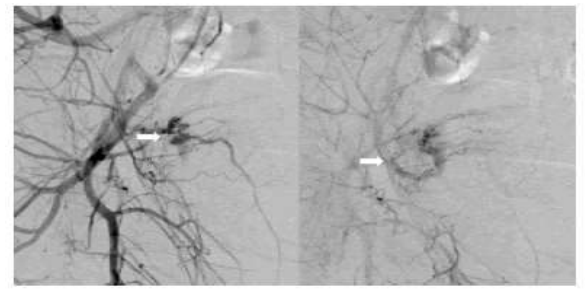

Shintre and Coelho [16] reported a 27-year-old lady who was known to have Thalassemia minor who had manifested with heavy vaginal bleeding and passage of clots over the preceding two days. She stated that she had been having continuous on and off mild to moderate vaginal bleeding pursuant to a second trimester therapeutic abortion she had undergone two months preceding her presentation. She did undergo therapeutic abortion in view of the fact that she had her chorionic venous samples which had shown that the foetus had Thalassemia major due to the fact that both herself and her husband had Thalassemia minor. The therapeutic abortion was induced with utilization of misoprostol (PGE1) tablets. The reports of the obstetrician who undertook the therapeutic abortion did document that the abortion was complete and therefore no curettage was undertaken pursuant to her abortion. She had also undergone another therapeutic abortion 8 months earlier for the same reason following chorionic villous sampling that showed Thalassemia major foetus. This therapeutic abortion was ensued by curettage of her uterine cavity for complete evacuation of her products of conception. She did not have any significant past medical or surgical history. She was noted to be pale or otherwise her general examination was normal. She had speculum examination of her vagina which showed a partially open cervical os that associated with minimal blood clots. There was no active bleeding. Her uterus was bulky, and it measured about 8 weeks to 10 weeks size as well as it was firm to soft in consistency, firm to soft with regard to consistency, mobile and associated with free fornices. The results of some of his laboratory blood tests included: Haemoglobin 9.5 grams per decilitre, platelets 3-lakhs, Serum Beta Human Chorionic Gonadotrophin (B-HCG) 35 MIU/ML which was normal, normal coagulation screen and normal liver function tests. Her blood sample was sent for grouping and saving for future use when required. She had ultrasound scan and magnetic resonance imaging (MRI) of pelvis. The MRI scan demonstrated a bulky uterus that measured 4 cm x 7 cm x 7 cm, heterogeneous lesion within the posterior wall of her uterus, lost endometrial-myometrial interface, multiple dilated tortuous blood vessels within her posterior myometrium which had suggested the likelihood of retained products of conception or gestational trophoblastic tumour which would represent placental site trophoblastic tumour, or uterine vascular malformation (see figure 1). The trans-abdominal ultrasound scan of pelvis did demonstrate an 8.8 cm x 7.5 cm x 7.5 cm bulky uterus the posterior myometrium that was very enlarged as well as heterogeneous with increased vascularity upon Doppler ultrasound scanning (see figure 2). Doppler ultrasound scanning did demonstrate a peak systolic velocity (PSV) of 121 cm / s as well as restrictive index of 0.36. The ultrasound scan also demonstrated that her endometrium was thickened within the lower uterine segment that was suggestive of retained products of conception. She had a chest x-ray which was normal. She had ultrasound scan-guided evacuation of her retained products of conception from her lower uterine segment which was sent for pathology examination. The evacuation of the products of conception did trigger active bleeding. She therefore underwent uterine artery embolization with utilization of cyanoacrylate (glue) (see figure 3). There was no evidence of active bleeding pursuant to her embolization. She was discharged on the 3rd post-procedure op day on oral antibiotics and haematinics. Pathology examination of the tissue did show degenerated and necrosed bits of decidua as well as few degenerate chorionic villi that were admixed with fibrin and blood. The degenerate products of conception did not show pathology examination features of placental site tumour trophoblastic. At her 6-weeks follow-up assessment she stated that her vaginal bleeding had diminished gradually over a period of 4 weeks and the bleeding stopped completely after 4 weeks. She had ultrasound scan of her pelvis with Doppler scan which did show diminished size of the arteriovenous fistula and with diminished vascularity (see figure 4). Shintre et al. [16] stated that the first case of AVM of the uterus was reported in 1926. [17]

Figure 3: Digital subtraction angiography (DSA) showing bilateral hypertrophy of uterine arteries that feed a tortuous, hypertrophic arterial mass with capillary lakes and post uterine AVM embolization film demonstrating successful embolization of the feeding vessels of AVM with the help of N-butyl cyanoacrylate (glue). Reproduced from: [16] Shintre H S, Coelho K S. Managing Uterine Arteriovenous Malformation (AVM) Is Like Dealing With Raging Wildfire Awaiting A Spark: Better Be Extremely Cautious & Be Ready With Counter Measures Like Uterine Artery Embolization (UAE). Obstet. Gynecol. Int. J. 2017; 6(1): 00195 DOI: 10.15406/ogij:2017.06.00195

https://medcraveonline.com/OGIJ/managing-uterine-arteriovenous-malformation-avm-is-like-dealing-with-raging-wildfire-awaiting-a-spark-better-be-extremely-cautious-amp-be-ready-with-countermeasures-like-uterine-artery-embolization-uae.html under copy right ©2017 Shintre, et al. This is an open access article distributed under the terms of the, which permits unrestricted use, distribution, and build upon your work non-commercially

Khan et al. [24] reported a 30-year-old G1P0010 lady wo had manifested with a 6 days history of abnormal bleeding from her uterus. Three months preceding her presentation, she had undergone a therapeutic abortion which was ensued by dilatation and curettage (D&C) for retained products of conception. Since then, she realised that she had developed a new onset of menorrhagia, which on the day of her manifestation had become persistent and which had become associated with severe pain, weakness, as well as dizziness. Upon her examination, she was observed to be hypotensive, and she had tachycardia. She had marked tenderness within her supa-pubic region. Her examination was otherwise normal. Some of the results of her laboratory blood tests included: haemoglobin 9.2 grams per decilitre, haematocrit 27.5% and negative serum Beta Human Chorionic Gonadotrophin (B-HCG). She trans-vaginal ultrasound scan which showed a 3.9 cm x 2.7 cm x 1.8 cm sized an-echogenic cystic spaces within the posterior wall of the fundus of her uterus (see figure 8). She had Doppler ultrasound scanning which revealed marked vascularity within her uterus (see figure 9). She had magnetic resonance imaging (MRI) scan of pelvis which showed a contrast-opacified structure within structure within the wall of her myometrium. Focal serpiginous flow voids were also demonstrated within the posterior-superior myometrium with extension to the canal of her myometrium (see figure 10). The features of the radiology were interpreted to be consistent with the diagnosis of arteriovenous malformation of the uterus (AVMU). She had uterine angiogram which confirmed features of arteriovenous malformation of the uterus (AVMU) within the posterior-superior wall of the uterus (see figure 11). The angiogram did demonstrate presence of multiple feeding arteries which had arisen mainly from the left with smaller arteries from the right side. Embolization of both uterine arteries was undertaken with utilization of Gelfoam (Pfizer, New York) pledgets to near stasis. She had a post-embolization arteriogram which demonstrated complete embolization of the AVMU as well as evidence of slow flow of contrast in both uterine arteries. No immediate complications emanated. Her vaginal bleeding stopped. She was discharged home on her 3rd day post-embolization. During her follow-up assessment, 3 weeks pursuant to her embolization there was no evidence of recurrence of abnormal uterine bleeding. The lesson that has been learnt from this case report is that embolization of the uterine artery supplying the AVMU is an effective minimally invasion option of treating AVMUs.

Figure 11: Left internal iliac artery angiogram revealing a hyper-vascular lesion within the uterine artery distribution with early venous filling during the late arterial phase: (A) early arterial phase (B) late arterial phase. Reproduced from: [24] Khan S, Saud S, Khan I, Achakzai B. Acquired Uterine Arteriovenous Malformation Following Dilatation and Curettage Treated with Bilateral Uterine Artery Embolization: A Case Report. Cureus. 2019 Mar 13;11(3):e4250. doi: 10.7759/cureus.4250. PMID: 31131173; PMCID: PMC6516630. https://pubmed.ncbi.nlm.nih.gov/31131173/ under Copyright © 2019, Khan et al. This is an open access article distributed under the terms of the Creative Commons Attribution License, which permits unrestricted use, distribution, and reproduction in any medium, provided the original author and source are credited.